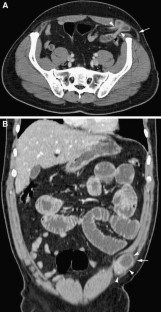

Fig. 3